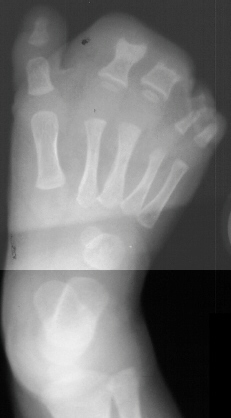

At age 12 months a girl presents severe overgrowth of the

foot. She was the product of a normal pregnancy and delivery and

is otherwise completely healthy. The parents main complaint is

that she can not be fitted with shoes. She had an amputation (image

1 & 2) of the 2nd and 3rd toes at the level of the mid diaphysis,

proximal phalanx and extensor tendon release of the 2nd and 3rd

toes with excision of abnormal fibrofatty tissue of right foot,